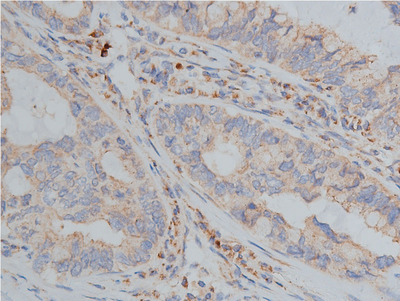

- 1:50 staining human lung carcinoma tissue by IHC-P. The tissue was formaldehyde fixed and a heat mediated antigen retrieval step in citrate buffer was performed. The tissue was then blocked and incubated with the antibody for 1.5 hours at 22°C. An HRP conjugated goat anti-rabbit antibody was used as the secondary.